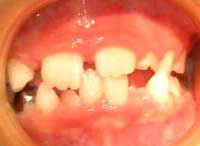

形成不全症とエナメル減形成

時々、保健センターの1歳半児検診で、虫歯を見て「これは形成不全」といわれ、直す必要はないですよ、といわれる患者さんがいるようです。「形成不全症」というのは遺伝性の病気で、エナメル質、または象牙質の元となる細胞がうまく作られなかったものです。お口中の全部の歯が茶色っぽくなったり白っぽくなったりします(右上下写真)。

検診した方が言いたかったのは「減形成」のことでしょう。減形成はエナメル質ができる(カルシウムが沈着して硬くなる)時の異常で、一本の歯、またはお口の中の一部の歯に起こります。原因はいくつかあります。

乳歯の場合はお母さんのおなかの中にいる時にエナメル質が硬くなりますから、お母さんの体が不調だった時期に対応して部分的に左右対称に茶色くなります。歯の表だけとか裏だけとか右の歯だけ茶色くなることはありません。

永久歯の場合ですが、先行する乳歯の異常に関係するものがほとんどです。その下にある永久歯が作られる時期にぶつけたり、進行した虫歯のために根の先に膿がたまった状態が続いていたりすると、エナメル質がうまく作られず、その時期に対応した部分が茶色くなります(右写真)。

下の写真のように歯の外側だけ、左右非対称の場所に茶色い穴が開いているのはやはり虫歯です。